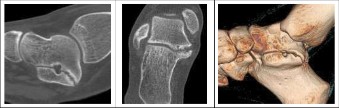

Thorough preoperative planning relies heavily on advanced imaging. While weight-bearing orthogonal radiographs of the foot and ankle are the starting point, they are often insufficient for complete surgical planning. Radiographic signs such as the "C-sign" (continuity of the talar dome and sustentaculum tali) and the "anteater nose sign" (elongation of the anterior process of the calcaneus) suggest TC and CN coalitions, respectively.

Computed Tomography (CT) is the gold standard for mapping the exact three-dimensional anatomy of the coalition. For TC coalitions, coronal CT slices perpendicular to the posterior facet are critical for calculating the percentage of joint surface involved. A coalition involving more than 50% of the posterior facet surface area is generally considered a contraindication to simple resection, as the remaining joint will likely be unstable and degenerate rapidly; these cases are better served by subtalar arthrodesis. Magnetic Resonance Imaging (MRI) is reserved for cases where a fibrous or cartilaginous coalition is suspected but not clearly visible on CT, or to evaluate the integrity of the surrounding cartilage and tendons.